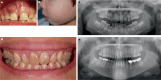

X-linked hypophosphatemia is a rare genetic disease caused by pathogenic variants in the PHEX (phosphate-regulating endopeptidase homolog X-linked) gene with X-linked dominant inheritance that causes metabolic bone disease and other severe complications. PHEX dysfunction results in increased production and secretion of the phosphaturic hormone fibroblast growth factor 23 (FGF23) from bone. The consequences of FGF23 excess are renal phosphate wasting and decreased calcitriol synthesis, leading to hypophosphatemia and subsequently rickets and osteomalacia. Children with XLH usually become symptomatic in the second year of life presenting with progressive disproportionate short stature, bone pain, frontal bossing, enlarged joints, bowed legs, and a waddling gait. Various other symptoms may develop later, including dental abscesses, peritonitis, hearing loss, pseudofractures, spinal stenosis, osteoarthritis, and enthesopathies, often leading to a diminished quality of life and ultimately disability. Here, we provide an overview of the current knowledge of the pathophysiology and treatment insights of this rare and challenging disease, including the targeting of FGF23 as a therapeutic approach that has significantly improved patient outcomes.